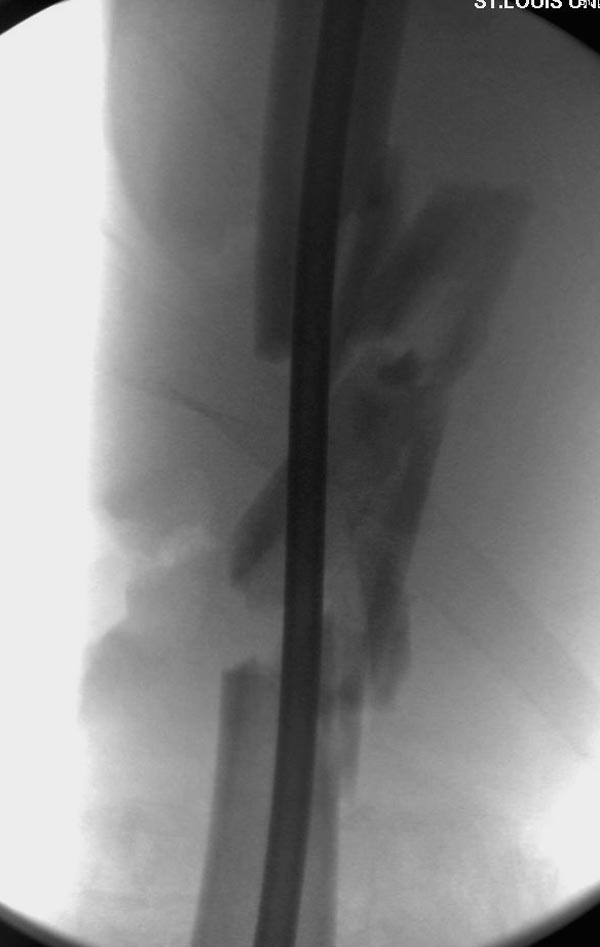

закончилась смертью трех остальных“боевых комрадов”. Начатую коллегой

открытую операцию на шейке пришлось закончить мне, установкой винтов и

ретроградной фиксацией бедра. Выписка в обычное сроки и наблюдался

несращения! По истечению 4 месяцев появились признаки варусной

деформации. На СТ срезах несращение шейки и бедра. Риминг, замена на

более толстый гвоздь и вальгусная остеотомия.